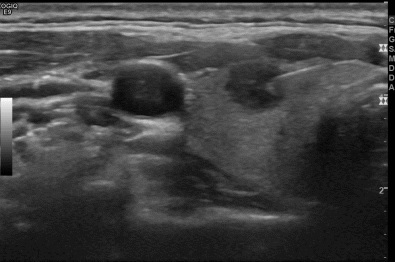

상기환자  외부 건진상 이상소견으로 내원하신 30대후반 여성분으로 의심스러운 갑상선 우엽 결절 세포검사진행후 갑상선암으로 진단되었습니다